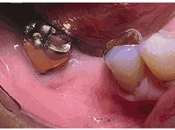

インプラント術前

右下奥の歯のないところにインプラントを埋め込みました。

これまで反対側の歯や前歯でしか食事ができずイライラしていたようですが、インプラントが入って以来、おいしく食事ができるようになったようです。